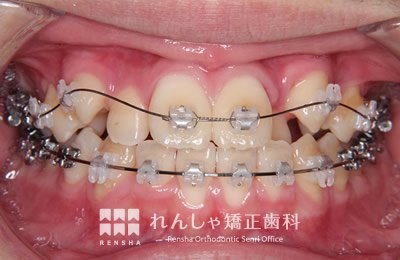

中高生

永久歯列はほぼ完成してしますが、歯列を側方だけでなく後方へも拡大し、埋まっていた右上奥歯を引っ張り出しています。

治療中

| 主訴 | 埋まったままでてこない歯がある |

|---|---|

| 診断名 | Angle Class II 小臼歯の埋伏と叢生を伴う上顎前突 |

| 初診時年齢 | 13歳5か月 |

| 装置名 | マルチブラケット装置 |

| 抜歯非抜歯 | 非抜歯 |

| 治療期間 | 2年3か月 |

| 費用の目安 | 約82万円+消費税(検査料金、都度の処置費用等も合わせた総額) |

| リスク副作用 | 歯の移動に伴う軽微な歯根吸収、歯槽骨吸収、歯肉退縮(本症例では軽度の歯根吸収を認めた)、矯正器具装着中のカリエスリスク増大(本症例ではカリエス発生無し) |